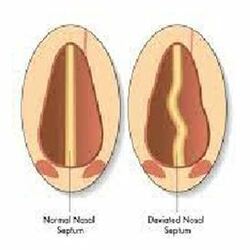

Septoplasty helps to straighten your nose by reshaping the wall between your nasal passages. If you have a crooked nose due to a deviated septum, your doctor will likely recommend septoplasty.

In addition to straightening your nose, septoplasty can also relieve nasal airway blockage caused by a deviated septum.

A Septorhinoplasty also known in the non-medical terms as (“nose job”) is a surgical procedure that involves operating on the bones and cartilage that give your nose its shape and structure and making your septum straight.

It has a two-fold objective to improve the appearance of your nose (Rhinoplasty) and to improve how you breathe through your nose (Septoplasty).